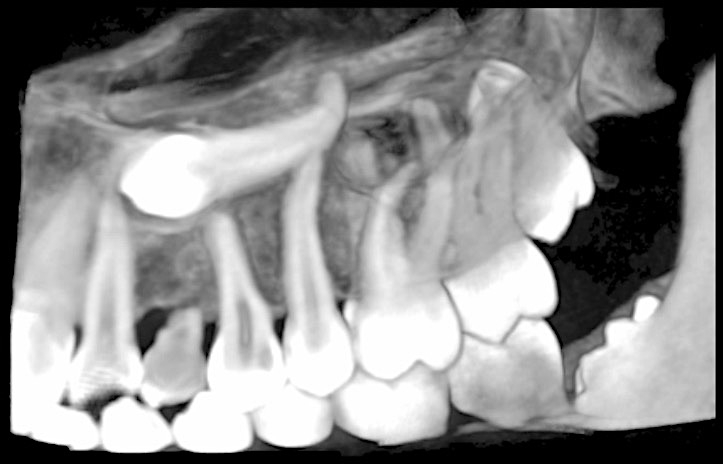

Un sujet concret et une approche pratique. Cette web conférence vous donnera les clefs de la prise en charge des dents incluses dans un exercice quotidien et réaliste.

Web conférence ayant eu lieu le Jeudi 8 avril 2021